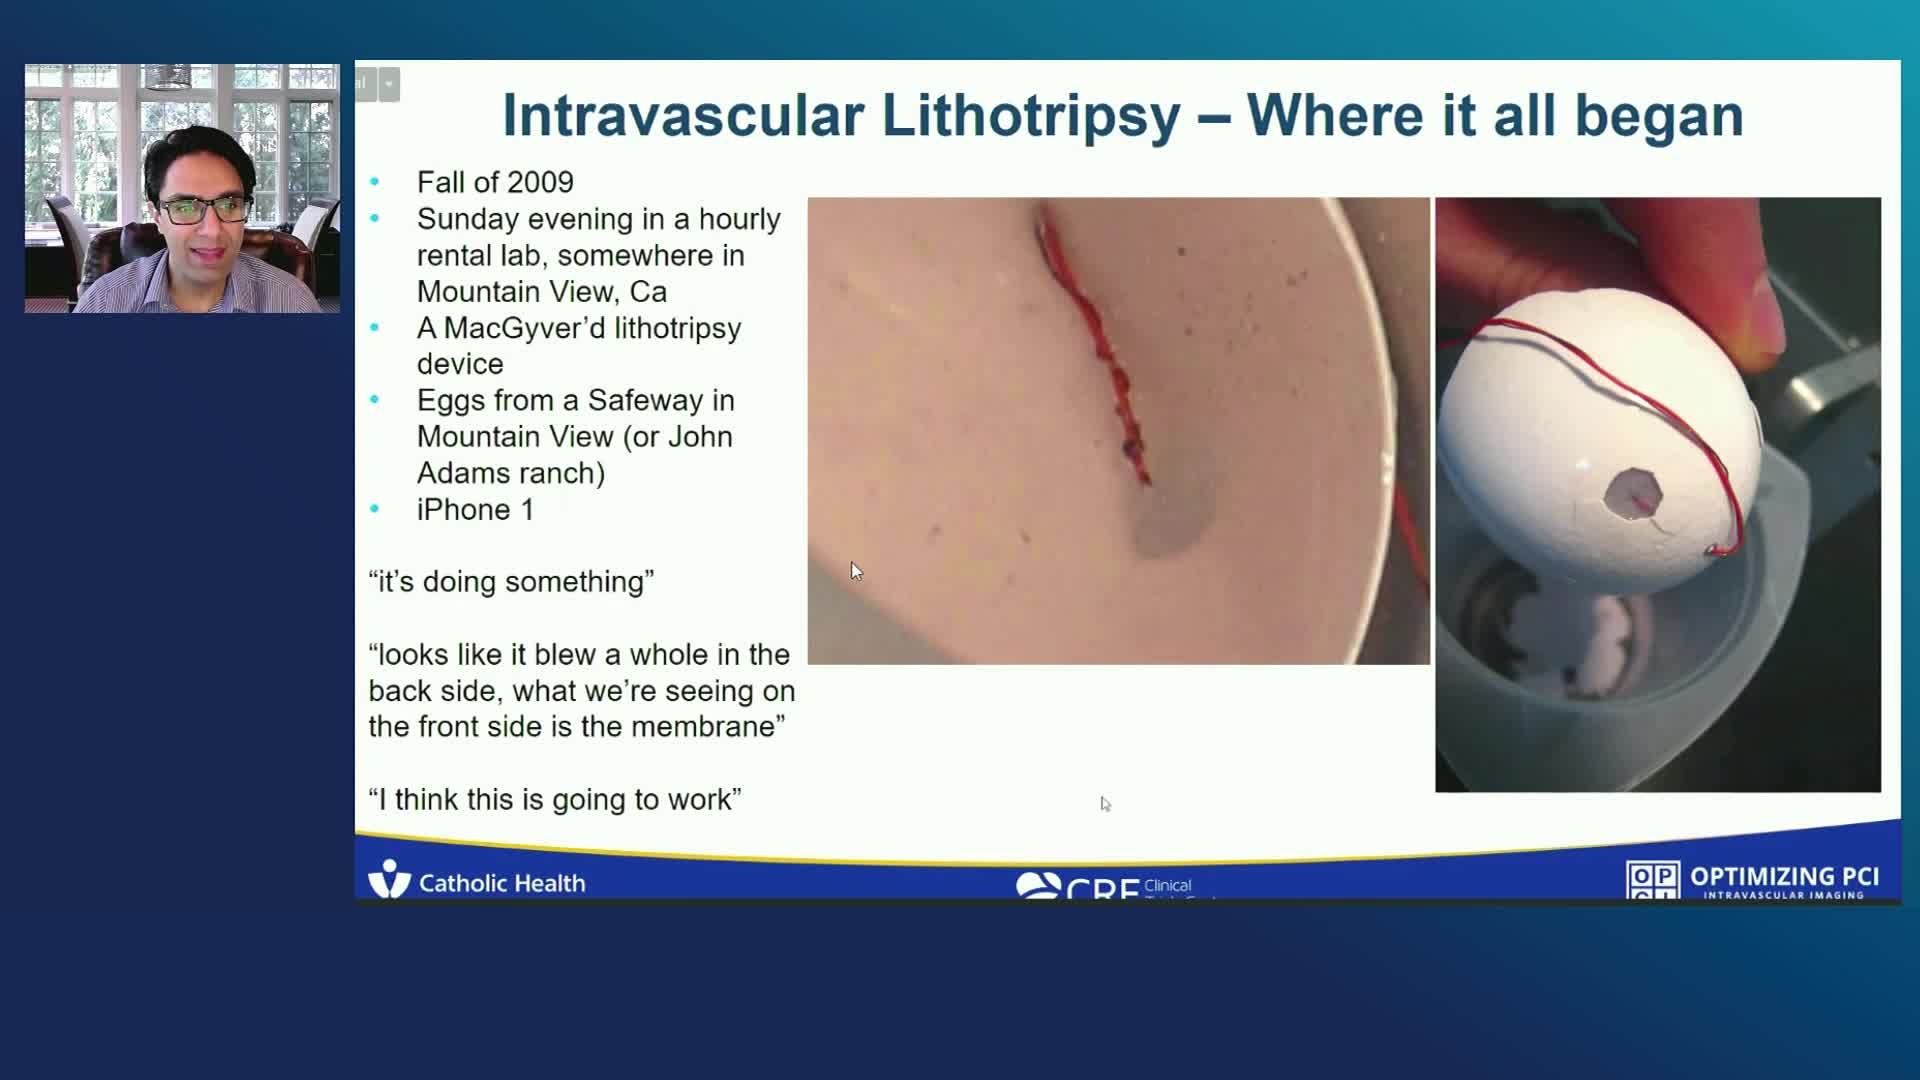

Shockwave IVL

Simplify your procedures with Intravascular Lithotripsy (IVL) by safely modifying intimal and medial calcium to achieve optimal outcomes while minimising trauma, complications and costs due to its unique MOA.

Coronary IVL Greatest Hits

Intravascular Lithotripsy for Treatment of Severely Calcified Coronary Artery Disease: The Disrupt CAD III Study